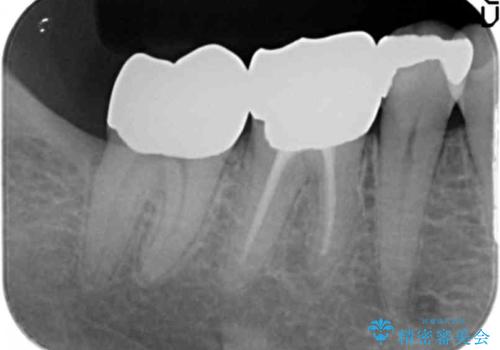

⑷最終形成、歯型とり

⑸クラウン装着

- 19万円(右下7 仮歯1万円、PGAクラウン 8万円、歯周外科手術(APF)10万円)費用は治療当時の料金となります

そうすることで、正確に歯型もとれ、精密なクラウンが製作でき、再度虫歯になる可能性を低くできます。